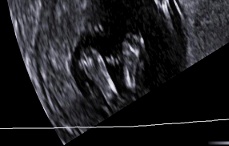

Прошли в 14нед первый скрининг, рассматривали всё около часа и подробно объяснили что и как,где.

Я хоть и сама врач, но в такой ситуации быть пациентом в тыс раз приятнее. И всё никак не отделаться от мысли удивительности происходящего, всего 8,5 КТР и живота-то толком нет, а там уже настоящий человек и всё у него есть и всё работает! Будто ты являешься частью какого-то великого таинства и исполнителем очень важной миссии что тебе доверили такое родное и крошечное чудо

А ещё сказали что мы очень похожи на мальчика по ПБ, но это уточнить будет возможно позже, да и интуиция моя никогда меня не подводящая-говорит об обратном. Пересматривали вечером уже с папулей нашим видео и фото. Люблю эту крошку ещё с //, а теперь ещё и так можно глядеть на наш маленький курносый профиль. 154 удара самого любимого маленького сердечка и фото наших сладких пяточек. Спасибо что дочитали

! даже не представляю какого они там размера, наверное не больше чем тут на экране, причём в фото случайно попали где нам окружность головки мерили и глазницы смотрели, вывернулся так вывернулся, потом уже увидела дома приятный сюрприз !

, но потом мы перестали вертеться и дали измериться, всё в норме.